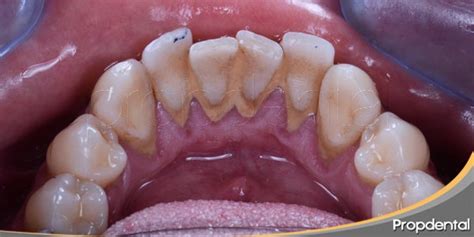

La acumulación de sarro en los dientes inferiores no es una coincidencia. Los dientes inferiores, especialmente los incisivos y caninos, están muy cerca de las glándulas salivales submandibulares y sublinguales.

El área detrás de los dientes inferiores, en particular, es propensa a la formación de sarro debido a la proximidad con las glándulas salivales.